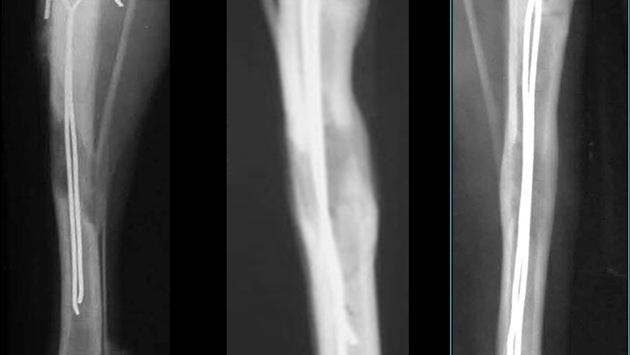

В ортопедическом Центре Илизарова в Кургане прошли стадию доклинических испытаний имплантаты, разработанные специалистами Томского политехнического университета. Они являются частью вариации аппарата Илизарова, применяемого для удлинения и исправления деформаций длинных трубчатых костей у детей. В ходе доклинических испытаний имплантаты помогли сократить сроки, необходимые для удлинения конечности, почти в два раза. Результаты исследований опубликованы в журнале Biomedical Materials. Советский хирург Гавриил Илизаров в середине 20 века разработал специальный аппарат для исправления пропорций тела, кривизны ног и разных деформаций костей. Его особенность заключалась в том, что фиксирующие кости элементы находились снаружи. Этот аппарат лежит в основе метода чрескостного остеосинтеза, который сегодня применяют более чем в 60 странах мира. Современный аппарат Илизарова состоит из титановых или углепластиковых стержней, которые фиксируются на конечности на пластинах различной формы и соединяются между собой подвижными штангами. За счет движения этих штанг врачи и корректируют рост кости. Имплантаты-спицы, разработанные российскими учеными, сделаны из традиционных для имплантологии материалов — стали и сплава титан-алюминий-ванадий. Однако ученые нанесли на них специальные покрытия. На стальные спицы были нанесены композитные материалы на основе пьезоэлектрического фторуглеродного пластика и гидроксиапатита. На титановые имплантаты исследователи наносили покрытие из фосфата кальция методом микродугового оксидирования. В случае с титановыми имплантатами и покрытием из гидроксиапатита мезенхимальные стволовые клетки реагируют на химический состав покрытия, и поэтому начинают дифференцироваться. А в случае со стальными имплантатами они реагируют на пьезоэлектрические свойства покрытия. «В случаях, когда кость нужно удлинить — например, когда у ребенка ножки разной длины — проводится рассечение кости, и ее части медленно раздвигаются. Разработанный нами имплантат представляет собой титановую или стальную спицу, он используется в качестве "проводника", помогающего сформироваться новой костной ткани. Такая спица вставляется внутрь трубчатой кости, — говорит один из авторов статьи, доцент Научно-образовательного центра Б.П. Вейнберга ТПУ Сергей Твердохлебов. — Такой имплантат помогает ускорить регенерацию кости, а, следовательно, и сократить срок реабилитации». На этапе доклинических испытаний специалисты Центра Илизарова прооперировали 24 собаки. Они сравнивали классические стальные, титановые имплантаты без покрытий и имплантаты с покрытиями. Испытания показали, что с применением томских имплантатов 4 см костной ткани восстанавливались за 35 суток, а с классическими имплантатами — за 70 суток. Понравился материал? Добавьте Indicator.Ru в «Мои источники» Яндекс.Новостей и читайте нас чаще.